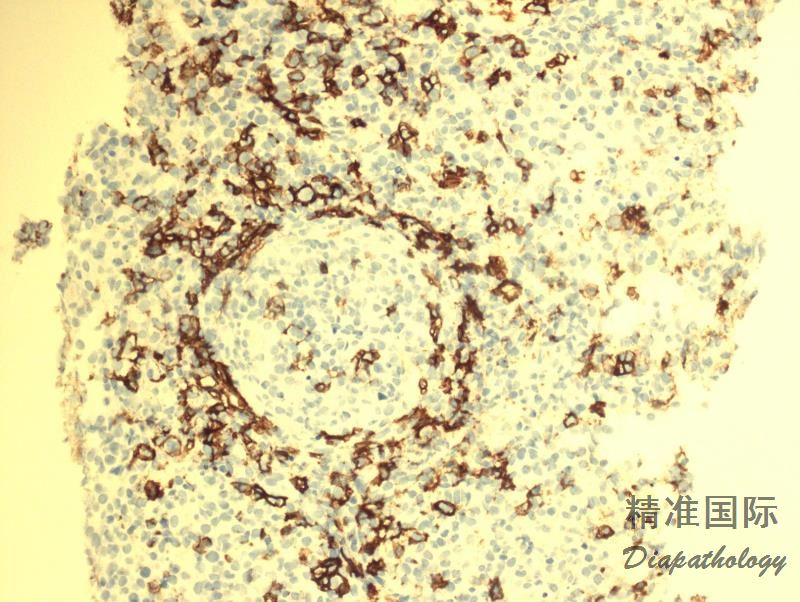

肿瘤细胞表达全 B 细胞抗 CD19. CD20. CD79a、PAX5,CD45+,CD30+/-,CD15-,EBER+;反应性小淋巴细胞表达 T 细胞抗原 CD3. CD5. CD4. CD8(CD4>CD8)。

免疫组织化学染色:

肿瘤细胞表达全 B 细胞抗 CD19. CD20. CD79a、PAX5,CD45+,CD30+/-,CD15-,EBER+;反应性小淋巴细胞表达 T 细胞抗原 CD3. CD5. CD4. CD8(CD4>CD8)